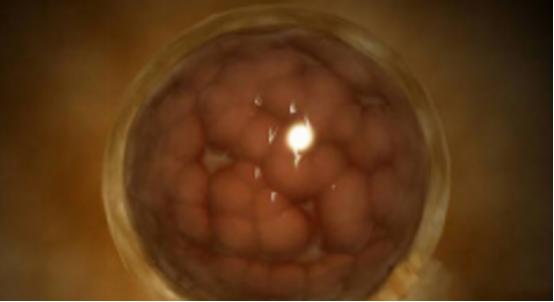

受精卵从输卵管分泌的液体中吸取营养和氧气,不断进行细胞分裂。与此同时,受精卵逐渐向宫腔方向移动,3~4天后到达宫腔时已发育成为一个具有细胞的实体,形状像桑椹,所以称为桑椹胚。

桑椹胚在子宫腔内继续细胞分裂形成胚泡(植入前胚胎的细胞数为30~200个),桑椹胚进入宫腔后1-3天透明带丢失(孵育),标志着植入(囊胚嵌入子宫内膜)开始。